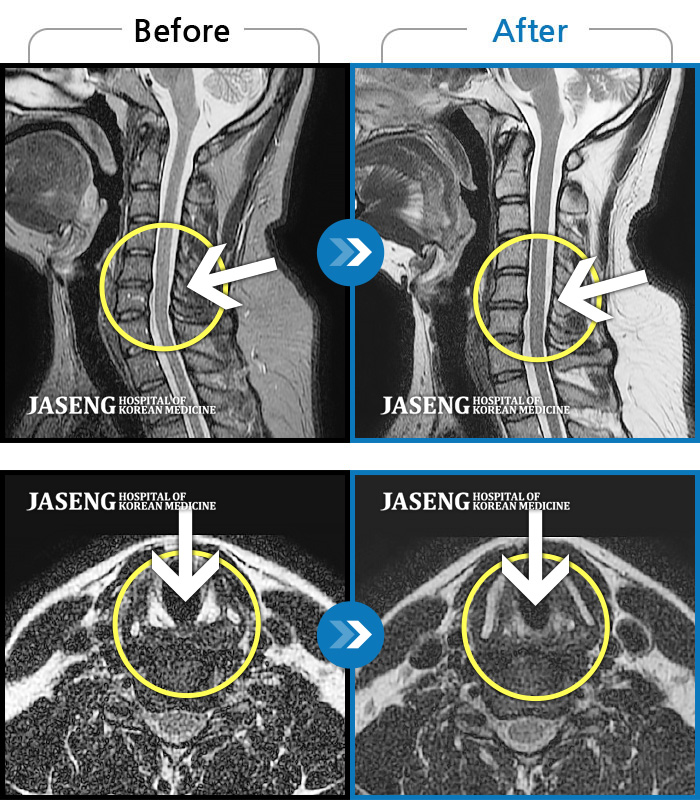

목디스크

도움받은 사례

인천 · 강아현 원장

좌측 목 통증 및 견갑내연 통증, 팔 전체 통증으로 일상생활에 어려움을 겪는 상태로 내원하셨습니다.

촬영시기

2023.11.27 ~ 2024.05.27

2024.06.03

조회수 481